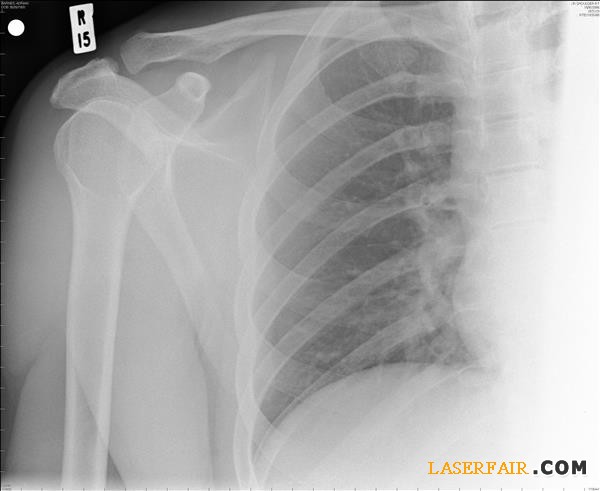

如今,很多非常先進和創新的醫療手術要依賴於(yu) 3D打印來填補受損的骨骼。“我們(men) 準備了一種基於(yu) 羥基磷灰石的液狀材料,可以通過3D打印機進行打印。”研究團隊的Vitaly Guzeev教授解釋說。他給出了一個(ge) 顱腦損傷(shang) 男性患者的例子。其受傷(shang) 部位經過3D掃描,然後將數據發送到3D打印機處,由其複製出受損失去的部分骨骼。這種“骨水泥”會(hui) 在3D打印過程中變硬。

此外,因為(wei) 該物質是從(cong) 動物骨骼中提取的,它保留了生物活性,並能夠“溶解”於(yu) 人體(ti) 內(nei) ,消失得無影無蹤。因此人體(ti) 可以適應它並且沒有排異的風險,並且其愈合速度遠遠超過傳(chuan) 統基於(yu) 幹細胞的移植或鈦植入物,據了解,後者在愈合完成後還需要通過手術移除鈦植入物。